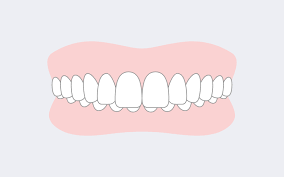

③切端咬合

切端咬合とは上下の歯の先が重ならずあたっている状態をいいます。

こちらも歯自体のものと骨格性に分かれます。

そのまま放置をすると歯と歯の先同士があたる状態が続くので歯に負担がかかり、歯の先が欠けてきます。

歯の先が欠けると前歯が短くなり、力が加わり続けると歯に亀裂が入り抜歯になる場合もあります。

歯の先が欠けるので、審美的な問題も発生します。